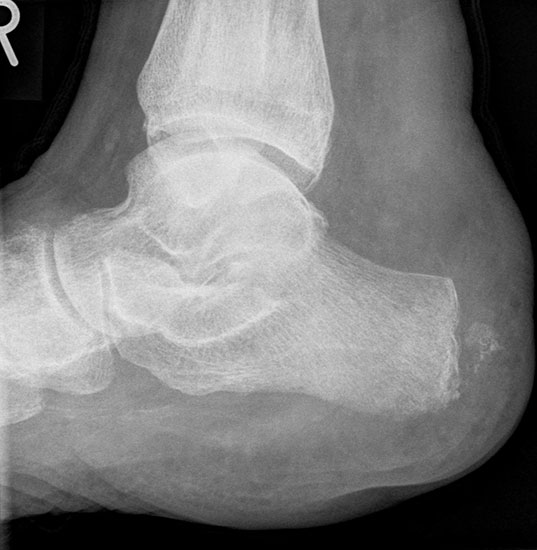

Exartikulation im Sprunggelenk (Symeamputation)

So weit bekannt, wird die Symeamputation in Europa im Gegensatz zu den USA relativ selten vorgenommen. Sie hat im Vergleich zur Unterschenkelamputation folgende Vorteile:

• Das Stumpfende ist wegen der breiten Knochenfläche und der erhaltenen Sohlenhaut endbelastbar, so dass der Amputierte in der Wohnung ohne Prothese einige Schritte gehen kann.

• Der erhaltene Unterschenkel verbessert die Gangökonomie, verglichen zur Unter­schenkelamputation.

• Die Prothesenversorgung ist technisch weniger aufwändig und leichter als bei einer Unterschenkelamputation.

Allgemein

Die operationstechnischen Anforderungen für die Syme-Amputation sollten nicht unter­schätzt werden. Die Symeamputation ist bei einer PAVK normalerweise nicht indiziert; wenn allerdings die A. tib. post. mit den calcanearen Ästen durchgängig ist, kann sie in Ausnahme­fällen vorgenommen werden. Ist die A. tibialis posterior verschlossen, die A. tibialis anterior aber intakt, kann eine „umgekehrte Syme-Amputation“ erwogen werden. Dabei wird ein ventraler Lappen gebildet, der nach dorsal umgeschlagen wird.